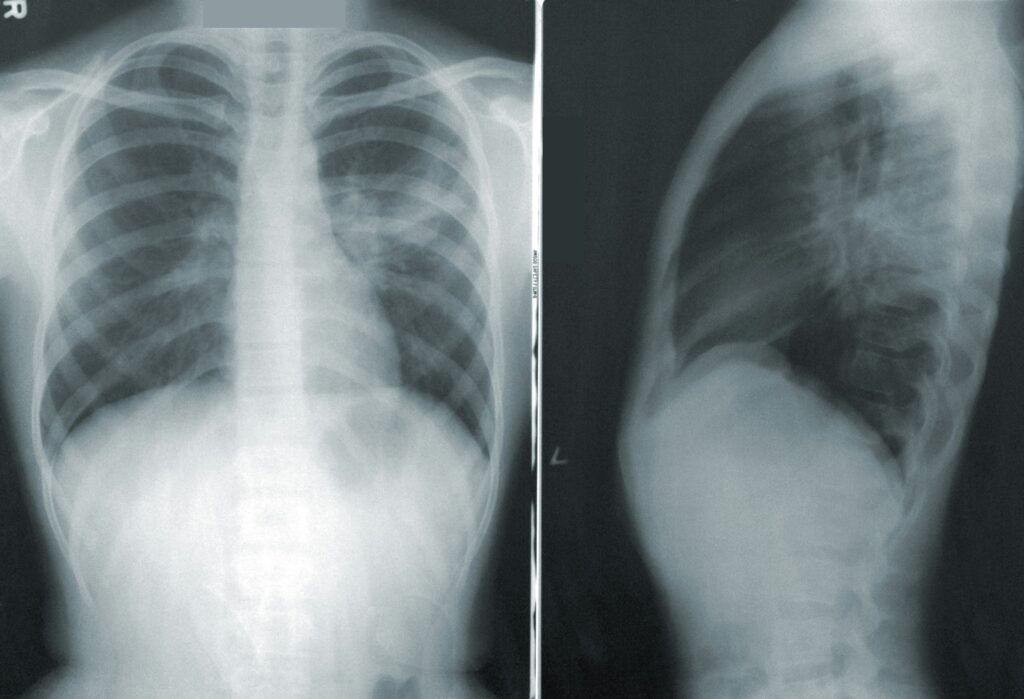

Not every stiff neck is the same. Treatment for the exact same diagnosis, called “cervicalgia,” may have very different treatment variations in Chinese medicine, regardless of what your Xray shows. Many contemporary physical therapists dismiss the idea that neck pain can come from sitting in a draft, simply because it is not a rigidly based in anatomical studies.

Again and again, I cannot emphasize to you enough the importance of imaging and testing… and at least a doctor’s screening. It’s always great to read books and discuss theory about anatomy, pain variations according to soft tissues and myofascial restrictions — but only after a potential serious condition is ruled out.